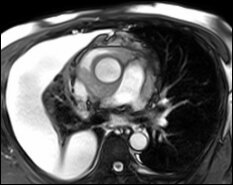

The Society for Cardiovascular Magnetic Resonance (SCMR) is holding the historic 20th Annual Scientific Sessions on February 1st through the 4th in Washington, DC, in 2017. The theme of this special event, Building on 20 Years of Excellence in CMR, will bring together experts from around the world to advance your knowledge of the field. Find out about exciting new sessions directed at clinicians, clinical researchers, physicists, engineers, and technologists. Learn about the role of CMR in patients with heart failure from this year’s outreach topic. Present, hear and discuss about the latest research in cardiovascular magnetic resonance, network with your peers and gain the insight you need to ensure positive patient outcomes. Daniel Messroghli, MD (Program Chair) Juliano de Lara Fernandes (Abstract Chair) |